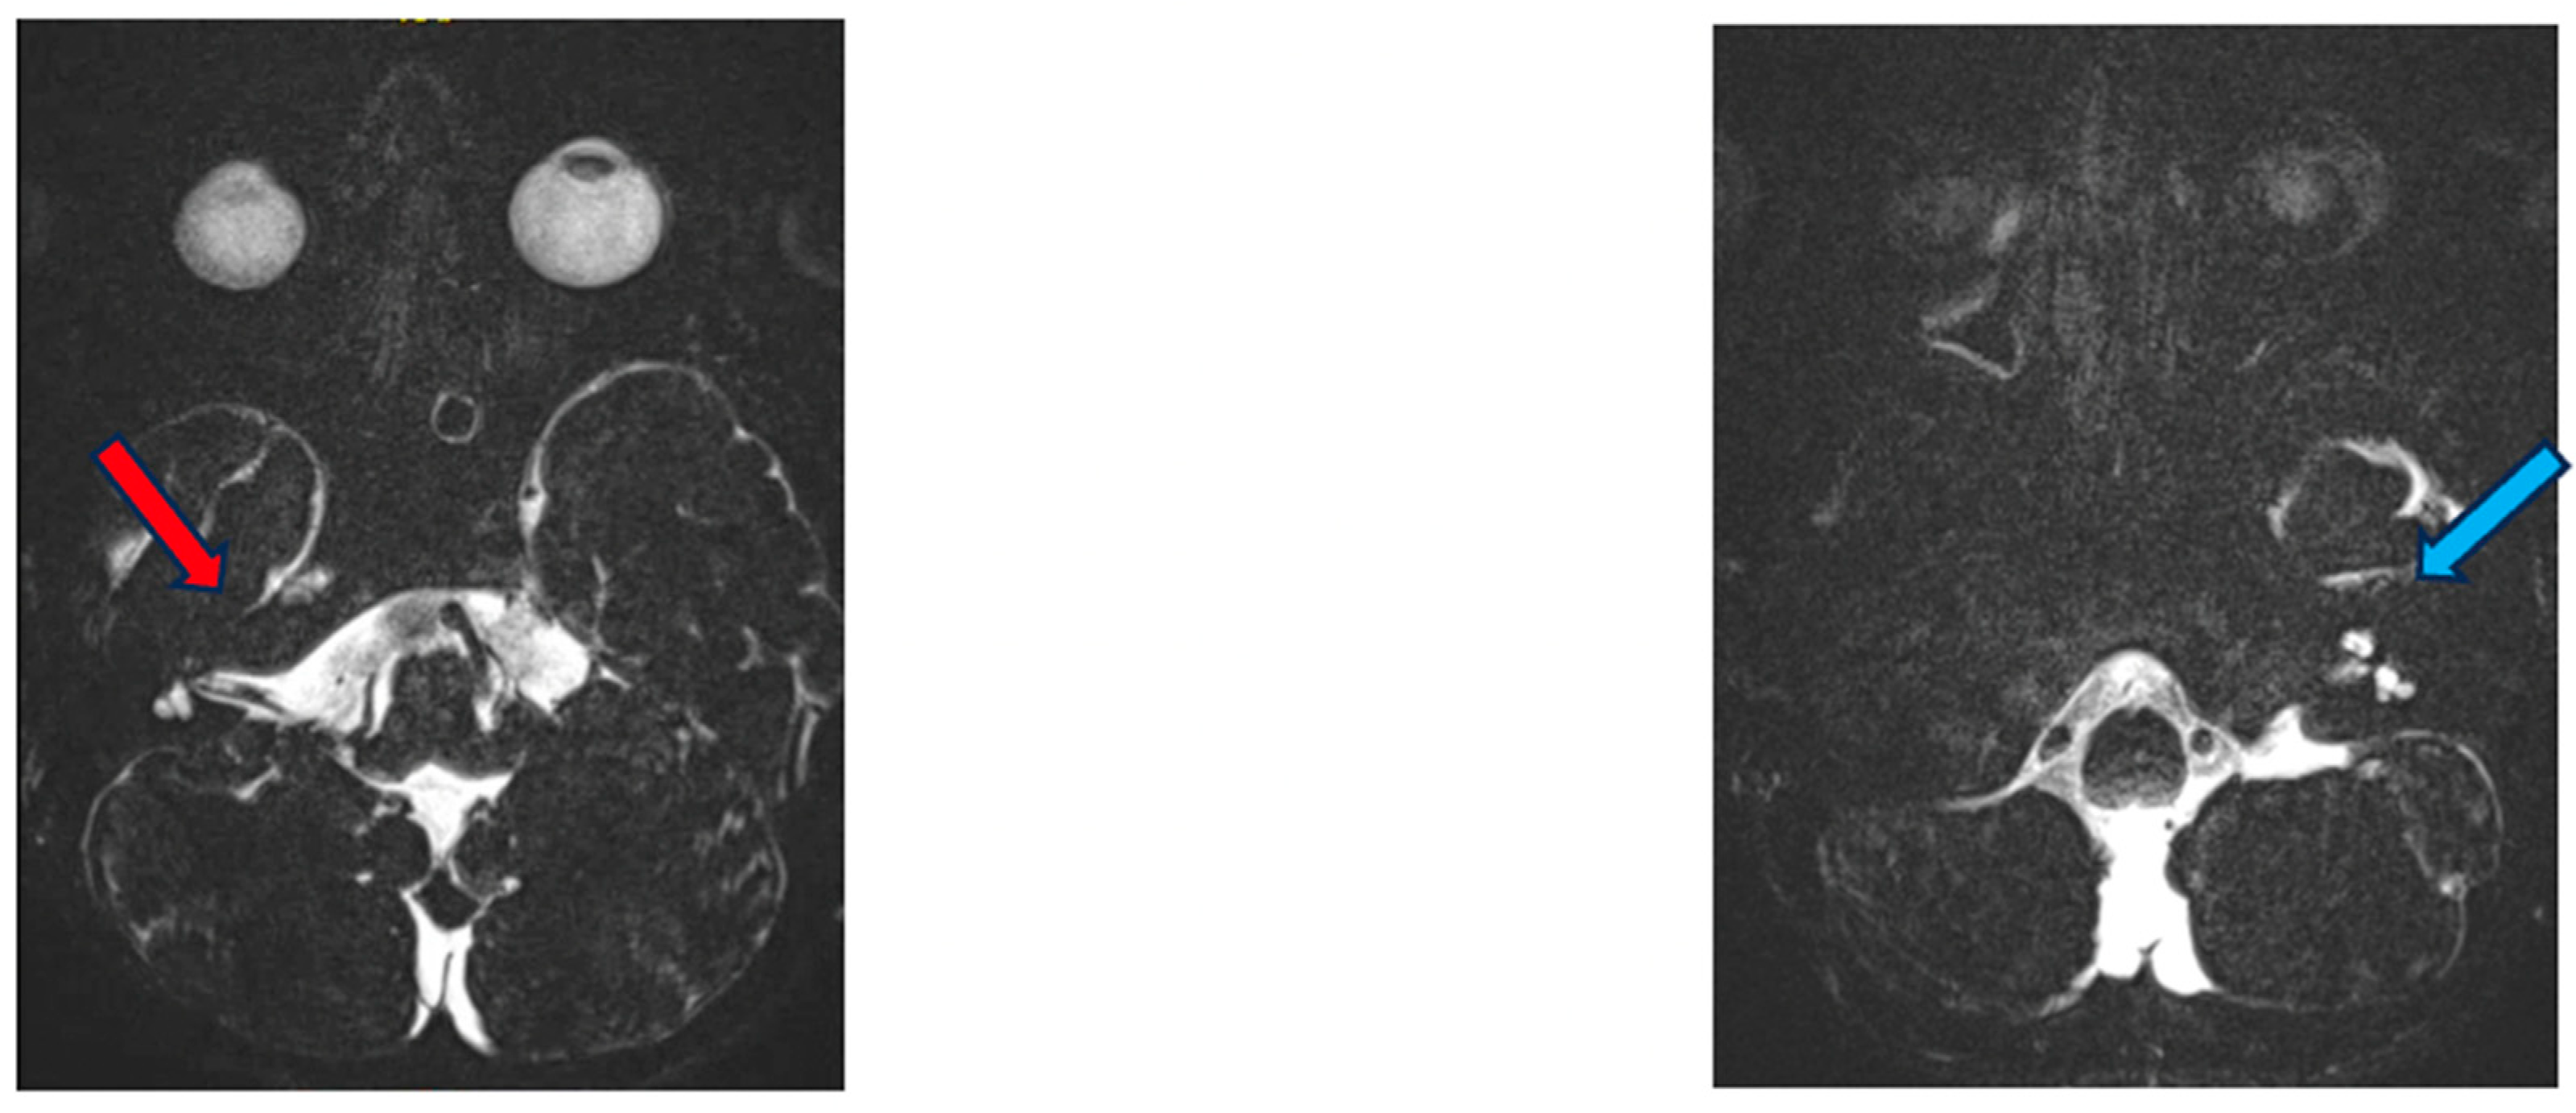

MRI revealed dysplasia of the lateral and posterior semicircular canals and the vestibulum bilaterally, with a normally constructed superior semicircular canal on the right and a smaller superior semicircular canal on the left. No dysplasia of the cochlea or intracranial abnormalities were evident (Figure 2).

Figure 2.

MRI of the inner ear for case 1, T2 tse3d weighted image, dysplasia of the lateral and vestibulum bilaterally (blue arrow depicts dysplastic canal on the left, red on the right).